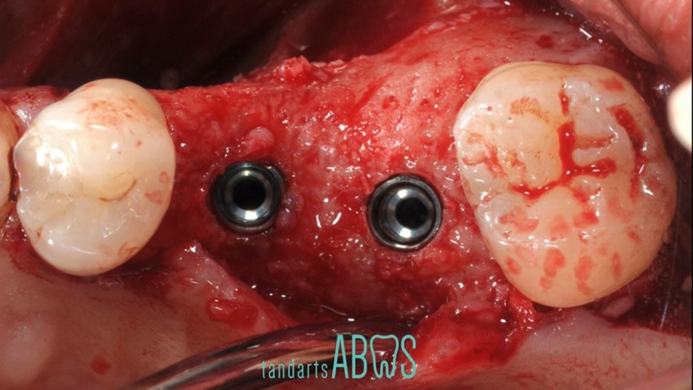

Clinical case: Installation of dental implants in complicated anatomic conditions using crest lifting methods

- Courtesy of Dr.Alexander Lysov, Russia -

Keywords

AnyRidge, complicated anatomic conditions, crest lift, MICA Kit, Dr. Alexander Lysov, bone regeneration, GBR, #26, maxillary posterior

Products:

AnyRidge implant system, MICA Kit